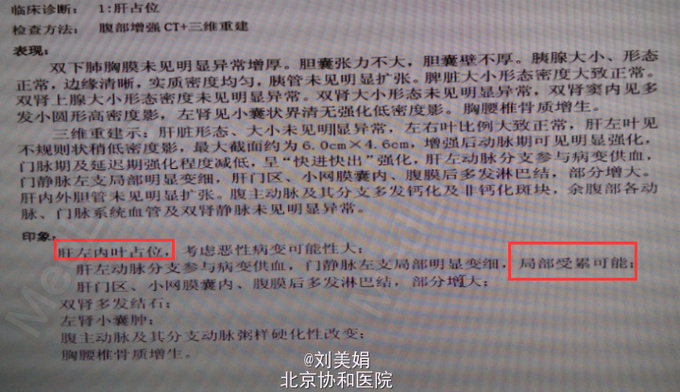

患者 男 58岁 主 诉:乙肝20余年,发现肝脏占位1月余 现病史:患者乙肝病史20余年,间断口服保肝药物,并定期复查肝功,肝功能目前可。每年常规行腹部B超检查,均未见明显异常。1月前体检,行腹部CT发现肝脏占位。患者无畏寒发热、腹痛腹胀、恶心呕吐、皮肤黄染等。于2015年7月10日我院门诊就诊,行腹部增强CT+三维重建示:肝左叶见不规则状稍低密度影,最大截面约为6.0cm×4.6cm,增强后动脉期可见明显强化,门脉期及延迟期强化程度减低,呈“快进快出”强化,肝左动脉分支参与病变供血,门静脉左支局部明显变细,肝门区、小网膜囊内、腹膜后多发淋巴结,部分增大。考虑:肝左内叶占位,考虑恶性病变可能性大;肝左动脉分支参与病变供血,门静脉左支局部明显变细,局部受累可能;肝门区、小网膜囊内、腹膜后多发淋巴结,部分增大。肝肾功:AST 67U/L,LD 254U/L,TBil 13.2μmol/L,DBil 4.5μmol/L,Cr(E) 79μmol/L,ALT 45U/L,Alb 48g/L,GGT 47U/L。

腹部增强CT+三维重建:肝左内叶占位,考虑恶性病变可能性大;肝左动脉分支参与病变供血,门静脉左支局部明显变细,局部受累可能;肝门区、小网膜囊内、腹膜后多发淋巴结,部分增大;双肾多发结石;左肾小囊肿;腹主动脉及其分支动脉粥样硬化性改变;胸腰椎骨质增生。